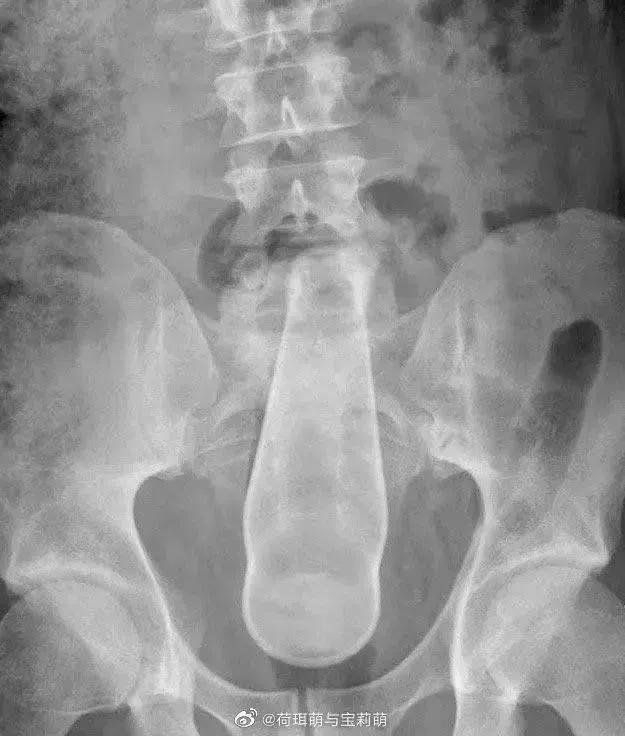

前段时间刷微博看到肛肠科医生发的X光照,一名男性的直肠里被塞入了一只足球。

是的,你没看错,就是国足怎么踢都进不了的那种,充好气圆滚滚的,如假包换。

像文章开头的那位兄台,就只能进行开腹手术了。虽然不能体验分娩的感觉,但可以体验一次“剖腹产”的痛感。